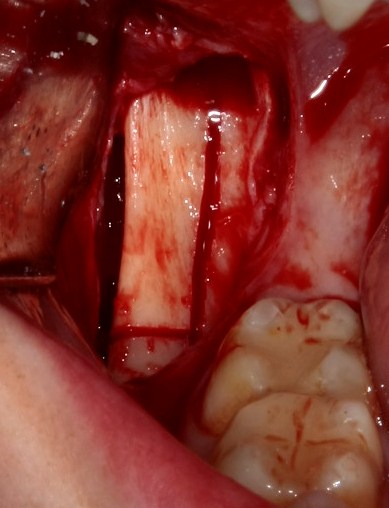

Вторая особенность — мы не адаптируем и не обрабатываем костный блок invitro, а фиксируем его так, как есть:

после чего обрабатываем — доводим до окончательной формы альвеолярного гребня:

Далее, можем приступить к установке имплантатов. Разумеется. по хирургическому шаблону:

Последняя картинка даёт представление о том, какой объем костной ткани мы «нарастили».

Поскольку принимающее ложе и аутокостный блок конгруэнтны, мы можем отказаться от использования барьерной мембраны. Она не нужна.